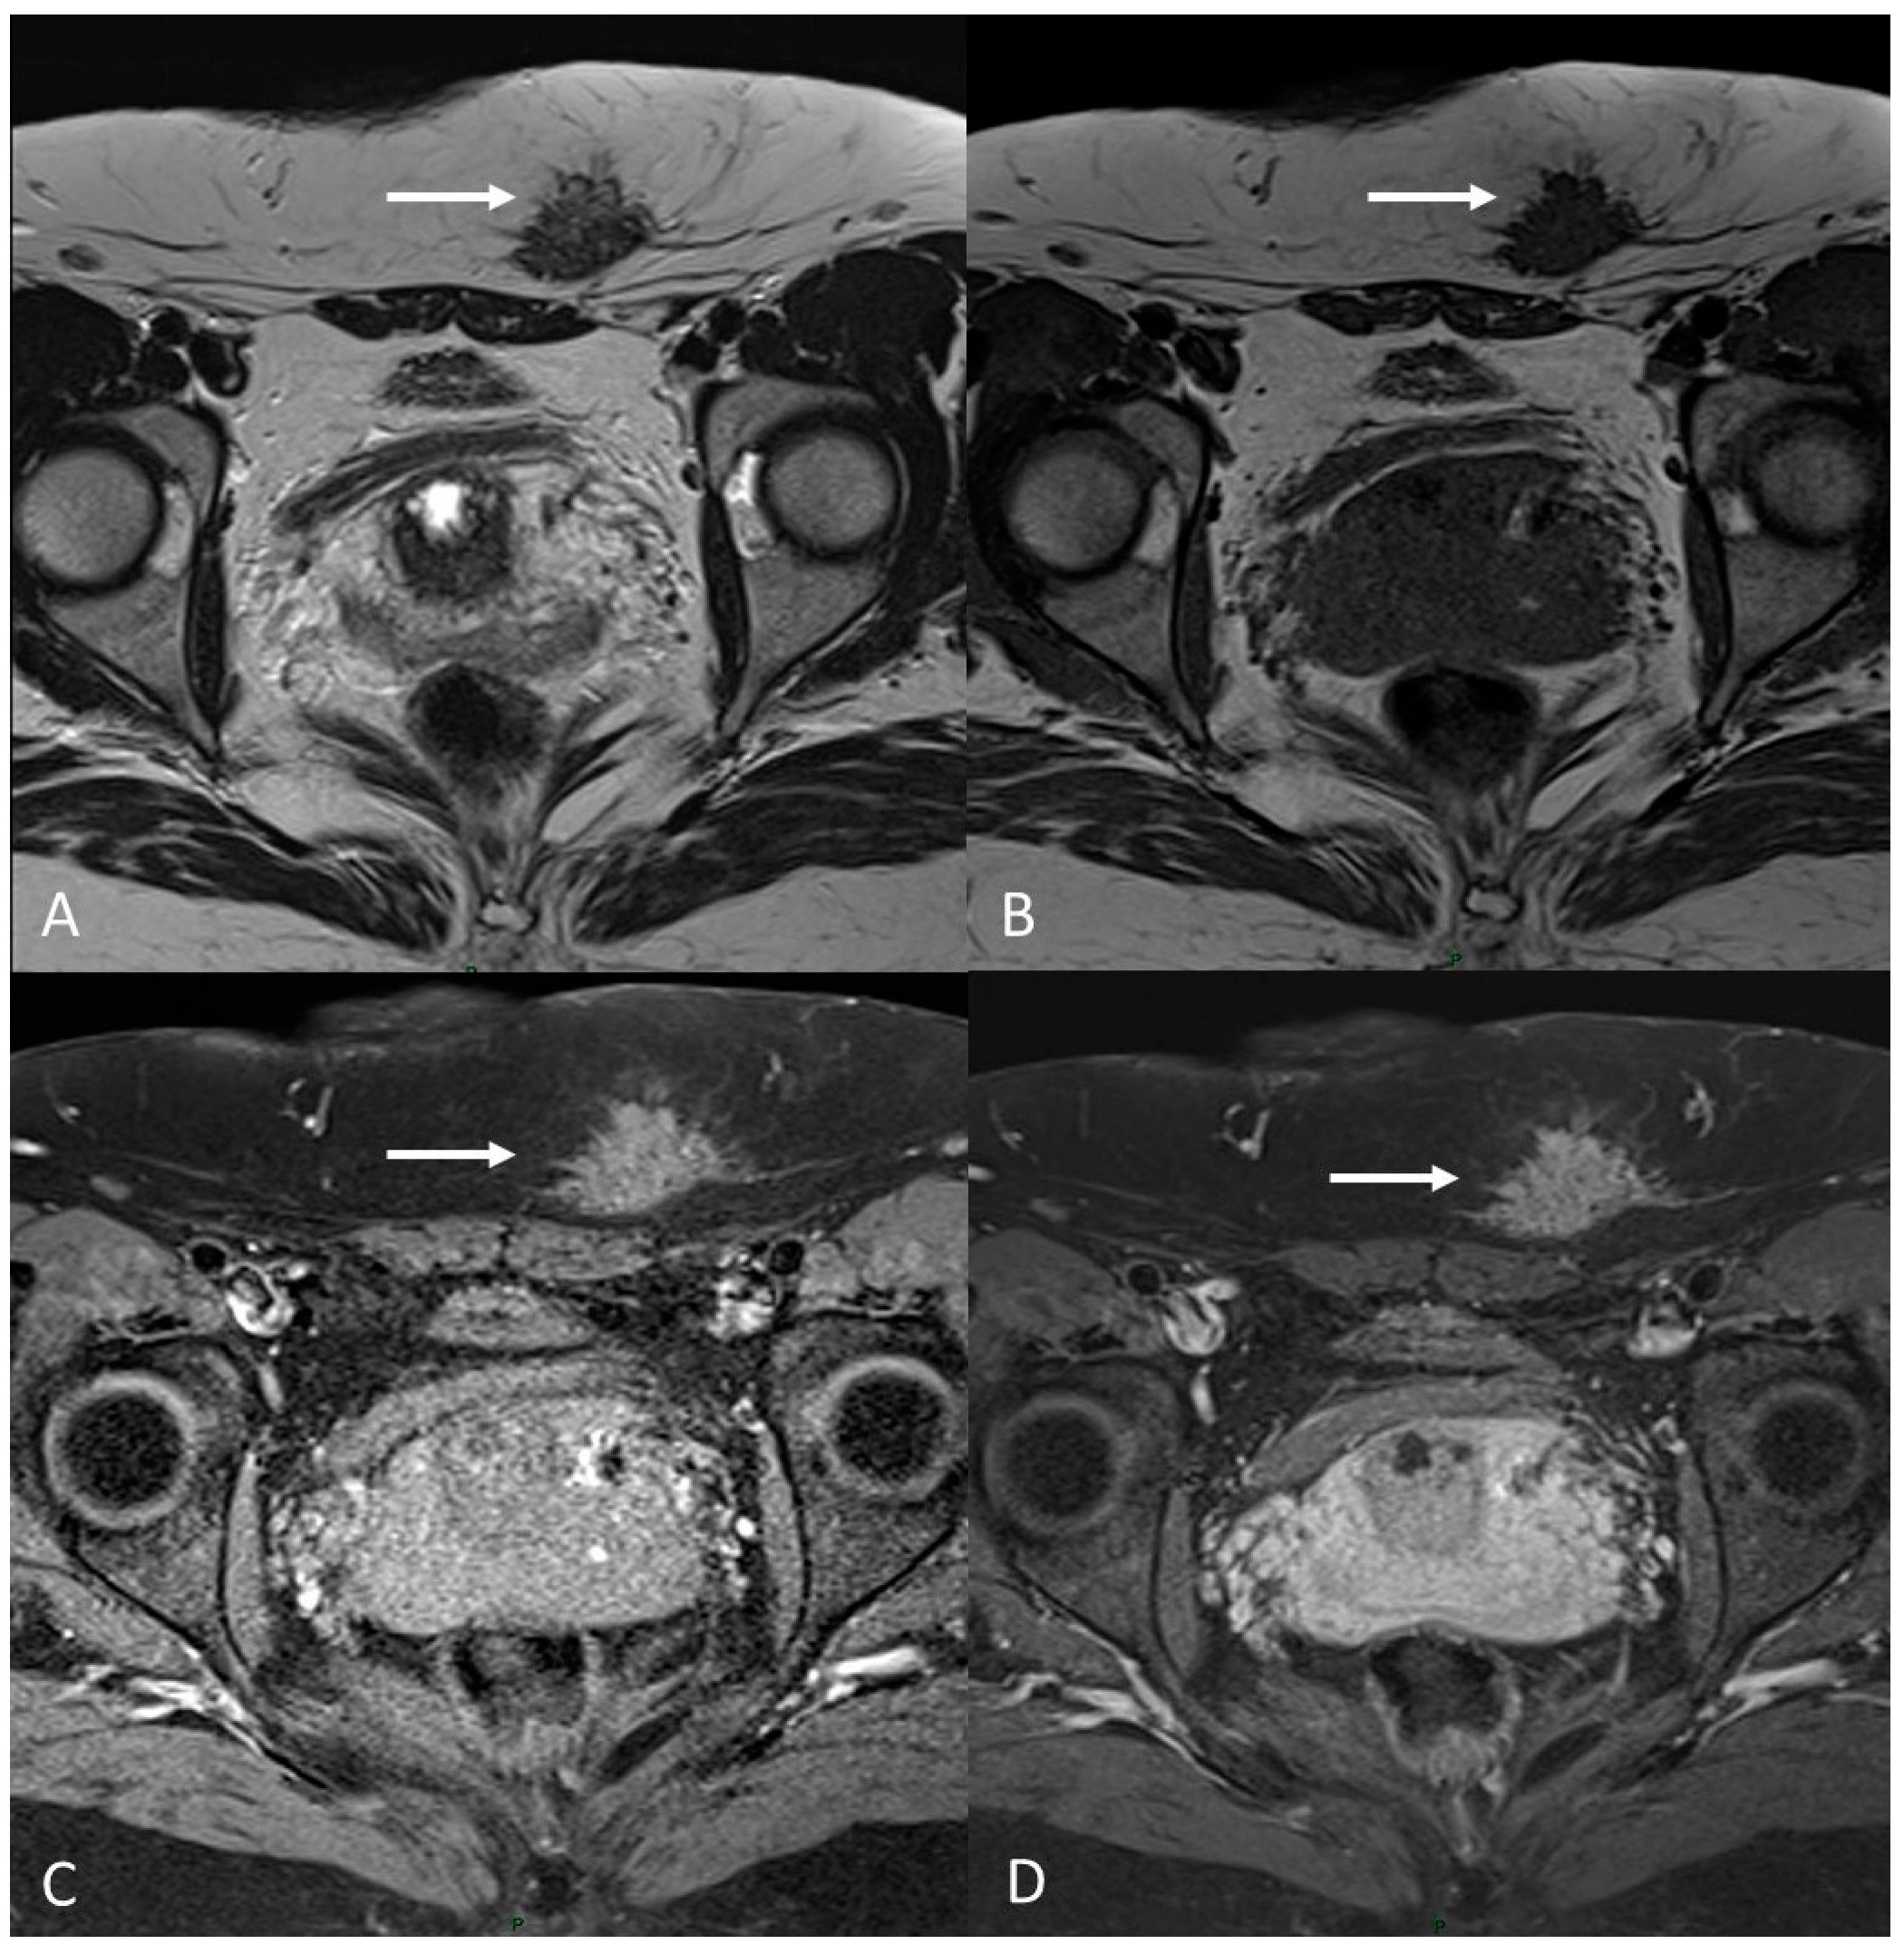

On an MRI, endometriomas appear as cystic lesions with different signal characteristics according to the age of the blood and the type of hemoglobin present.

Generally, they appear hyperintense on fat-suppressed T1WI and T1WI (Figure 7 and Figure 8). The hyperintensity on fat-suppressed T1WI helps differentiate endometriomas from dermoid cyst and teratoma, which usually contain fat [51]. On T2WI, a variable signal can be obtained: a hypointense signal can affect variable portions of the cyst, sometimes also presenting a stratification, until a complete loss of the signal. This is called the shading sign and is correlated to the different state of hemoglobin degradation [52] (Figure 8). The T2 dark spot sign refers to hypointense spots in the wall of the cyst due to the presence of macrophages (Figure 9).

Figure 7.

Ovarian endometrioma in a 37-year-old female. (A) Axial T1WI; (B) Axial fat-suppressed T1WI. Typical aspect of an ovarian endometrioma (white arrows).

Figure 8.

Right tubo-ovarian endometriosis in a 25-year-old female patient with reported localized abdominal pain in the right iliac fossa, which increases intensity during the menstrual cycle. (A) Axial T2WI; (B) Axial fat-suppressed T1WI. Enlarged right adnexal cyst with incomplete septa denoting dilated tube (white arrows). The cystic content shows low signal intensity on T2WI and high signal intensity on fat-suppressed T1WI, consistent with hemorrhagic fluid.